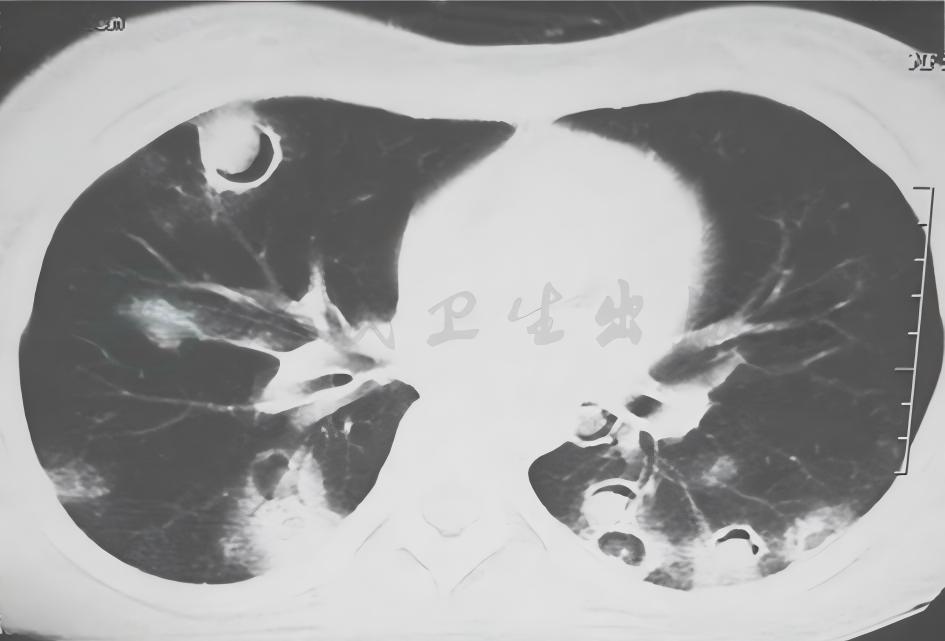

图6韦格纳肉芽肿胸部CT表现

女性患者,21岁,间断咳嗽2个月,诊断为韦格纳肉芽肿。胸部CT可见双肺多发结节影伴空洞形成,各结节影与血管关系密切